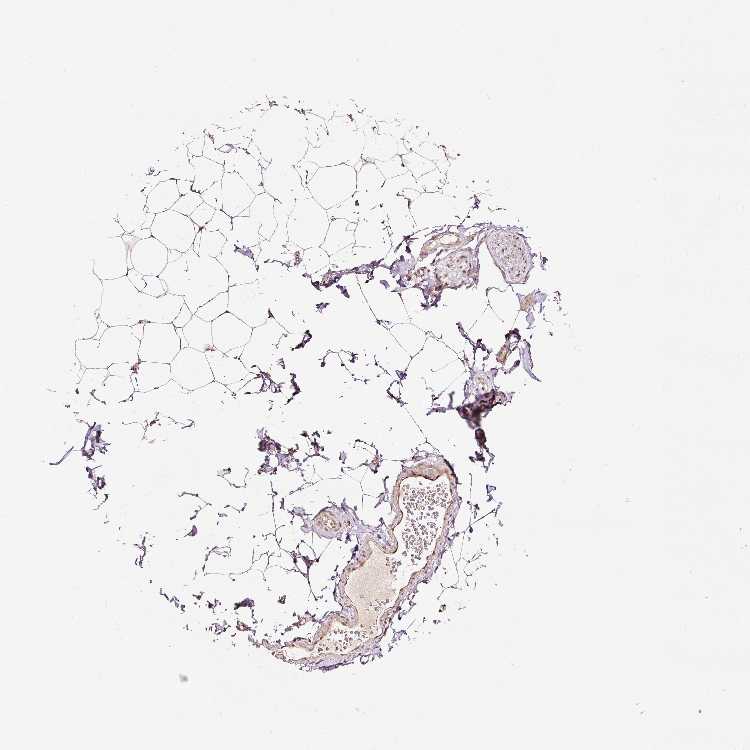

ADIPOSE TISSUE - Antibody stainingi

Antibody staining in the annotated cell types in the current human tissue is reported as not detected, low, medium, or high, based on conventional immunohistochemistry profiling in selected tissues. This score is based on the combination of the staining intensity and fraction of stained cells.

Each image is clickable and will lead to virtual microscopy that enables deeper exploration of all samples and also displays staining intensity scores, fraction scores and subcellular localization as well as patient and tissue information for each sample.

Antibody HPA049123Antibody HPA058507Antibody CAB004557

Adipocytes LowNot detectedMedium